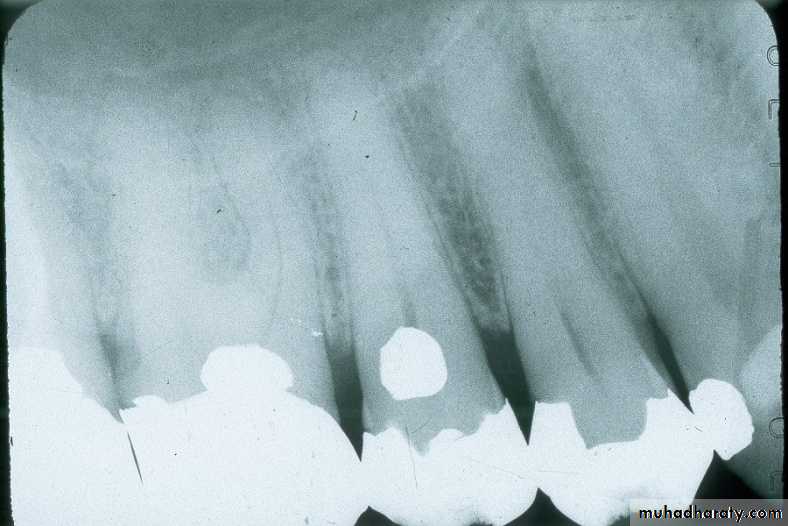

Mandibular Premolar

film equidistant from lingual surface of teeth (red arrows); film placed toward center of mouth, displacing tonguefront edge of film anterior to middle of canine; approximately centered on 2nd premolar

centered on second molar

Mandibular Molarfilm equidistant from lingual surface of teeth; in this case the film will usually contact lingual of molars